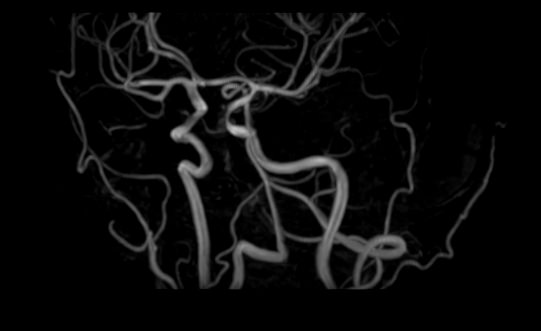

Стандартная МРТ головного мозга дает важную информацию о состоянии и структуре мозговой ткани для выявления большого числа заболеваний, в том числе опухолевых образований, демиелинизирующих заболеваний, воспалительных процессов головного мозга и мозговых оболочек. Стандартную МРТ головного мозга дополняет МР-ангиография, которая отображает состояние системы кровоснабжения головы и шеи. Компьютерная программа обрабатывает данные, полученные при сканировании, и формирует объемные изображения как самого мозга, так и сосудистой системы в отдельности без прилегающих тканей. Обе методики применяются одновременно и взаимодополняют друг друга, давая полную диагностическую картину.

Исследование предоставляет информацию о состоянии тканей головного мозга и оболочек, проходимости кровеносных сосудов, наличии и размерах опухолей, тромбов, гематом и других патологий. Изучив изображения, нейрохирург или другой специалист получает информацию о локализации патологии, степени повреждения тканей мозга, может принять решение о проведении операции либо контролировать ход лечения.